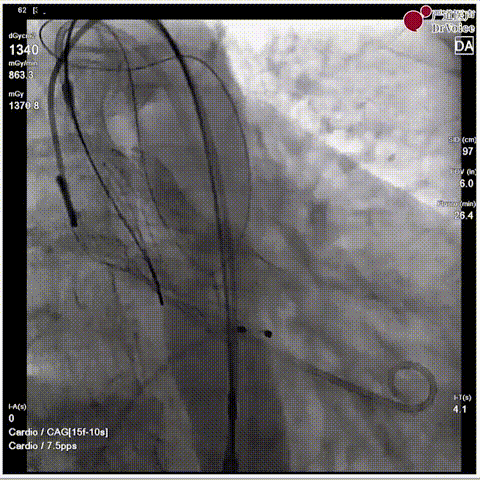

手术瓣膜释放后造影(4例)

病例一

病例二

病例三

病例四

快速过弓跨瓣(4例)